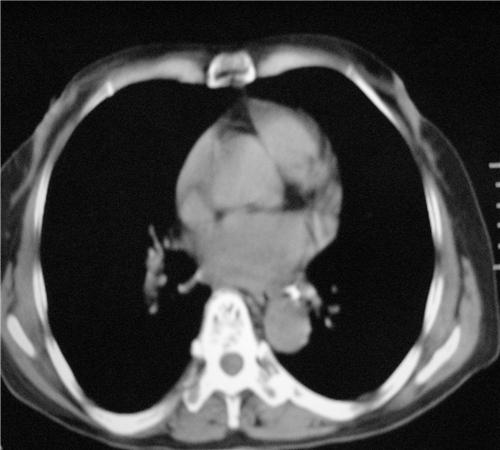

标题: CT26849:女67岁反复胸痛两天余,临床考虑夹层。 [打印本页]

标题: CT26849:女67岁反复胸痛两天余,临床考虑夹层。

右肺感染,未见夹层。

升主动脉增宽是怎么回事啊!食管有事吗?老师

既然考虑夹层,建议强化!另:右下肺感染!

1)右肺感染性病变。2)建议行ct增强扫描或mri检查排除主动脉夹层。

双下肺感染,右侧显著。有无夹层,增强扫描后再诊断。

1. 感染性病变,2.未见夹层,3.食道未见异常。

平扫未见确切夹层征,建议必要时增强扫描或mri检查。